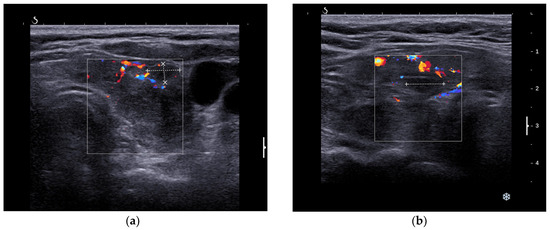

3.1.2. Thyroid Ultrasound

3.2.2. Thyroid Ultrasound